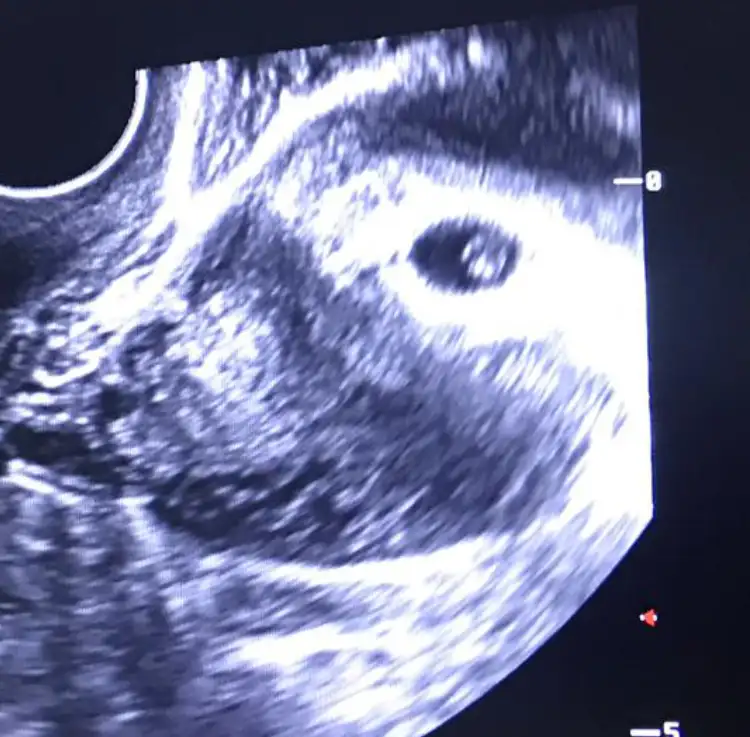

Bende çabuk acıkıyorum, ama yemek yiyemiyorum kokusu fena rahatsız ediyor. Sanki gün geçtikçe koku hassasiyetim artıyor. Ama ilerledikçe daha da mı artar. İlk gebeliğim olduğu için hiçbir fikrim yok5+3 oldum canım. 6.haftaya adım atar atmaz inceden başladı. Acıkmazsam yani midem kazınmazsa iyi gidiyorum ama saat başı atıştırıyorum minik minik. Bugün öyle yaptım en azından yoksa betim benzim atıyor...![]()